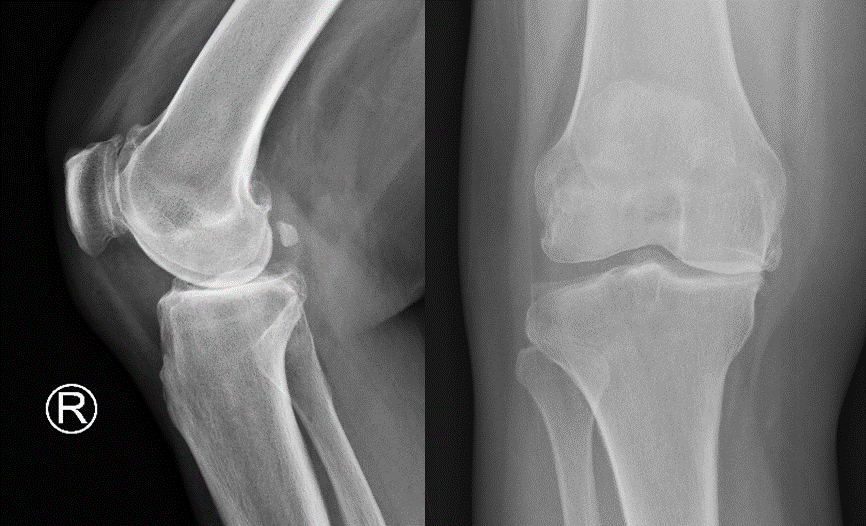

患者杨阿姨右膝疼痛已持续7年之久,近6个月来病情明显加重,严重影响日常生活。巧合的是,杨阿姨的亲属曾在21年前因为同样的疾病经姜为民主任诊治后完成过膝关节置换术,至今功能仍然良好。鉴于亲属的经历,杨阿姨此次慕名找到姜为民主任。姜主任仔细了解病情并综合评估后判断杨阿姨膝关节大量骨赘增生,关节间隙狭窄,需要接受关节置换手术。